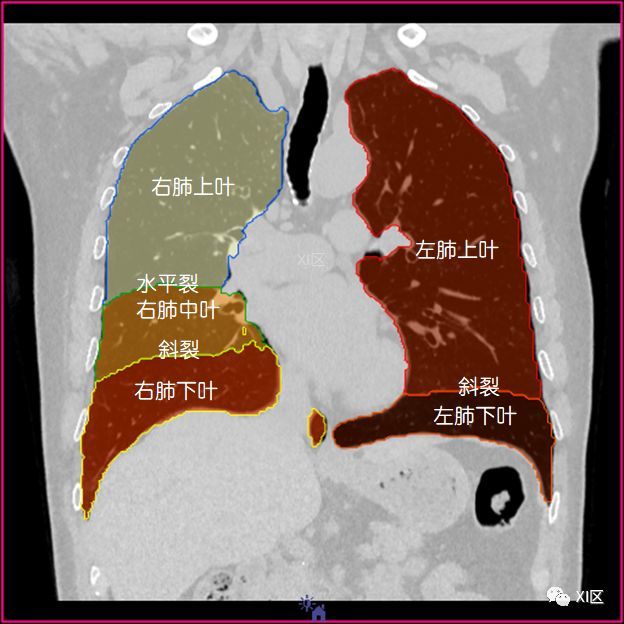

如此详细的肺部影像解剖,有点儿酷

如此详细的肺部影像解剖有点儿酷